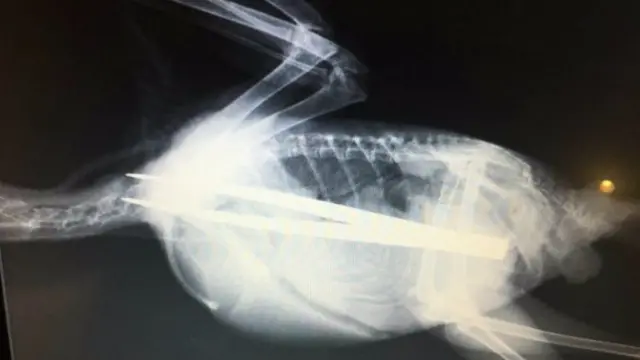

RSPCA vets in Nantwich dealt with one of their most “incredible cases” when a young jackdaw pecked off more than it could chew. , external

Image source, RSPCA/Nantwich News